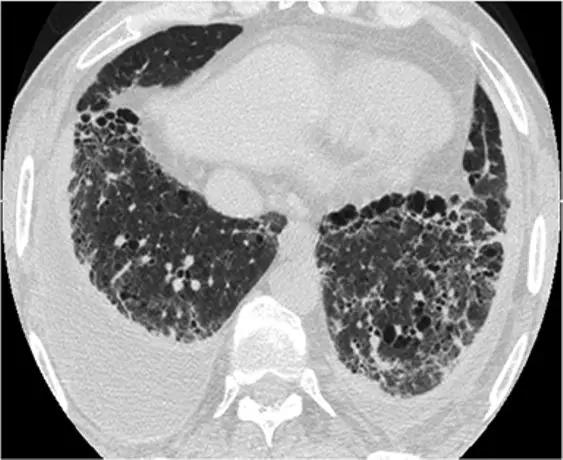

肺组织细胞增生症在处于纯囊性期(纯结节性和结节性-囊性期之后的第三期)时模拟LAM。它的特征是存在薄壁和厚壁的囊、形状呈异形,类似于苜蓿叶。囊肿具有特征性以上部和中部肺区分布为主。

*组织细胞增多症。上叶水平的HRCT揭示了一种“囊肿型”,其特征是许多薄或厚的“真”囊肿,形状奇异,大小不一。在右胸膜腔中发现引流导管以治疗气胸,这是这位27岁重度吸烟患者。